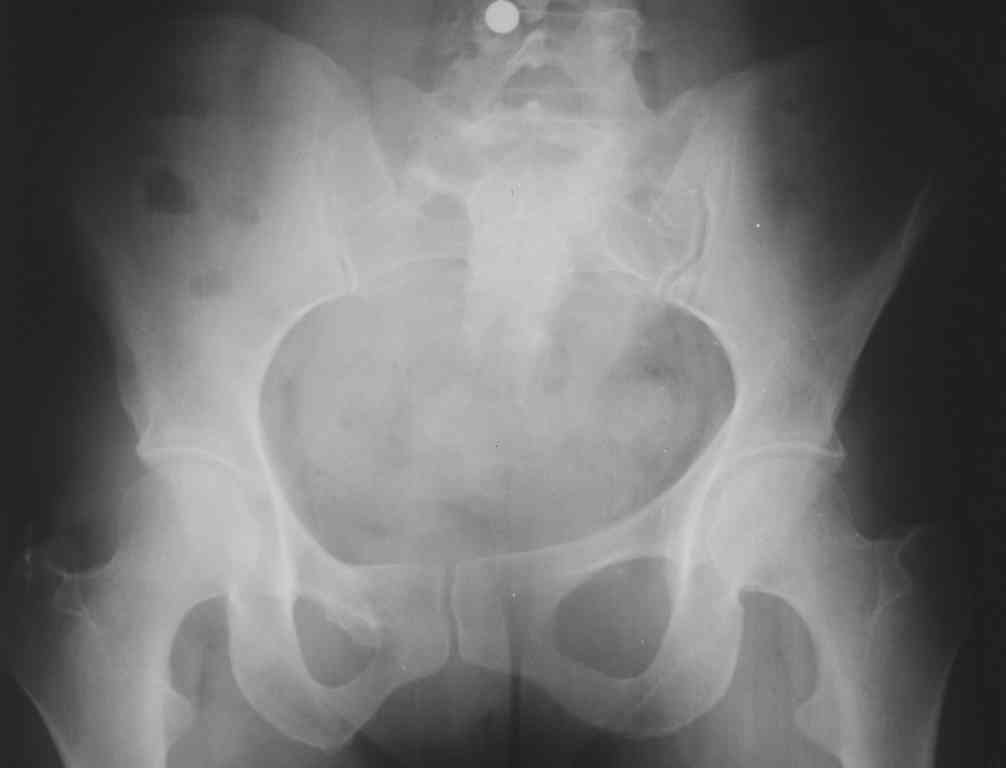

К нам в клинику поступила пациентка 30 лет с диагнозом: Постравматическая ротационная стабильная деформация тазового кольца.

Относительное укорочение левой н\конечности на 1 см. Левосторонний компенсаторный сколиоз 2 ст. Болевой синдром.

С марта 2003 года жалуется на боли в тазу, ппояснице усиливающиеся при движении. В настоящее время жалобы на боли в области крестца, КПС больше слева, в пояснично-крестцовом отделе позвоночника. неприятные ощущения, щелчок при выпрямлении правого тазобедренного сустава из положения полного сгибания. боли в тазу появляются при ходьбе ч\з 100 м, так же при вставании из положения сидя, после сидения в течении 2-3 часов. при ходьбе более 100 м появпяется зябкость стоп больше справа. ходит при помощи трости в правой или в левой руке. без трости боли появляются сразу после начала ходьбы.

симптомы натяжения с обеих сторон отрицательны. С 2003г. лечится консервативно, получала ЛФК, массаж, физиолечение - без эффекта. в 2005г. лечилась в санатории с ортопедическим уклоном, получала плавание в минеральной воде, магнитотерапия, массаж, ЛФК. отмечала умеренное улучшение в течении 2 недель. Вопросы: надо ли оперировать, т.е. устранять относительное укорочение левой н\конечности и как?Если не оперировать, то как лечить консервативно? Р-граммы, КТ прилогаются.